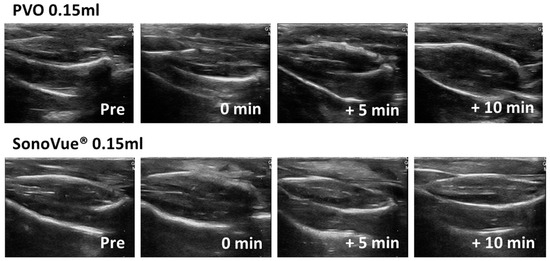

3.2. Contrast Enhanced Ultrasound Image Using PVO and SonoVue® in Sham Group